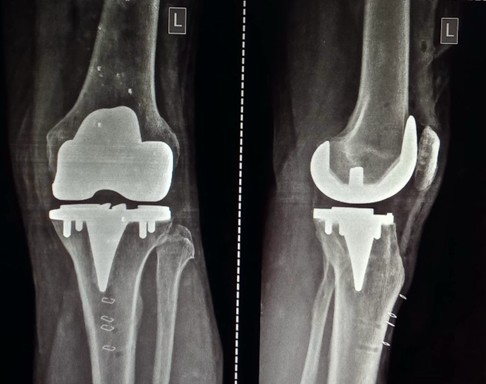

Post-operative x-ray. Intra-operative stressed laxity and limb alignment, and post-operative stressed laxities and limb alignment were assessed.